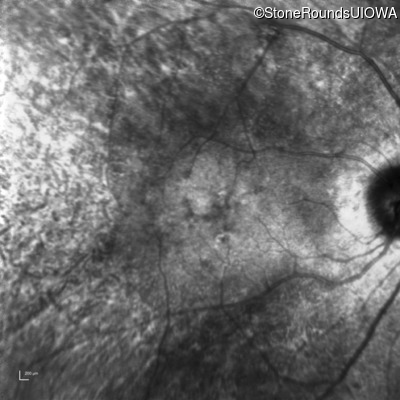

Infrared Fundus Photograph - Left - 20/70 +1

Exemplar